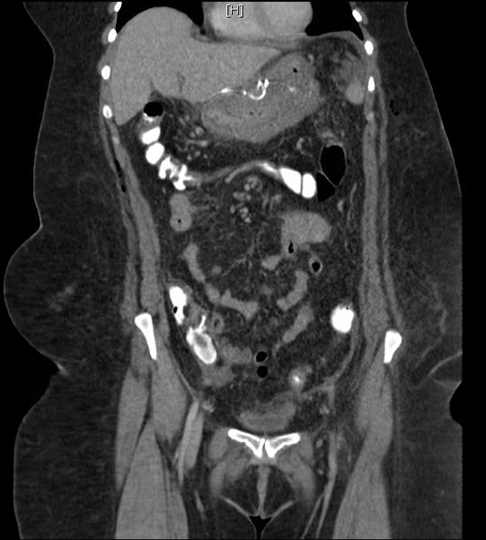

A 50-year-old female presented with a past medical history of gastroesophageal reflux, hypertension, hypothyroidism, inflammatory polyarthropathy, and obesity with a BMI of 44 kg/m2. Her surgical history included tonsillectomy, hysterectomy, cholecystectomy, and left knee replacement. Her medications included omeprazole, plaquenil, levothyroxine, and liothyronine. The patient underwent laparoscopic Roux-en-Y gastric bypass and hiatal hernia repair. She tolerated the procedure well, was functioning within normal limits, and was subsequently discharged on postoperative day-1. The patient was doing well on her follow-up appointment on postoperative day-5 where she was tolerating 80 oz of fluid a day; well above the minimum requirement. However, a few hours later the patient developed severe cramping epigastric pain, nausea, vomiting, and presented to the emergency department. The patient had a CT scan of her abdomen and pelvis, which showed obstruction at the level of jejunojejunostomy. There was no evidence of a leak or abscess (Figure 2). After intravenous fluid resuscitation, an X-ray of the abdomen and pelvis was performed eight hours later and showed transit of contrast into the ascending and transverse colon (Figure 3). However, given the lack of resolution of her symptoms, she was taken to the operating room urgently. A diagnostic laparoscopy was performed revealing a single adhesion of her jejunojejunostomy down to the base of the mesentery, effectively torsing the distal Roux limb. An adhesiolysis was performed. The patient recovered well, tolerated fluids, and was discharged one day later. However, at her follow-up appointment 12 days post Roux-en-Y and six days post adhesiolysis, the patient again developed nausea, vomiting, epigastric pain and dysphagia. She denied fevers, was not tachycardic, and had no signs or symptoms suggestive of infection. An outpatient Gastrografin swallow test was performed. The films were interpreted as showing no evidence of anastomotic obstruction or leak. However, it was suggestive of significant narrowing of the gastrojejunal anastomosis site and marked distal esophageal dysmotility as there was a five-minute delay of transit from the distal esophagus into the gastric pouch (Figure 4). Due to her persistent symptoms and impaired oral intake, the patient was directly admitted to the hospital.

Figure 2: Abdominal computed tomography with oral contrast revealing a markedly edematous postoperative stomach with dilated proximal loops of bowel to level of jejunal anastomosis, and adjacent mesenteric edema with small amount of free fluid, compatible with partial bowel obstruction. Taken on postoperative day-5. (A) Arrowhead: JJ staple line white arrow: Dilated Roux limb black arrow: distal decompressed small bowel (B) White arrow: Dilated Roux limb.